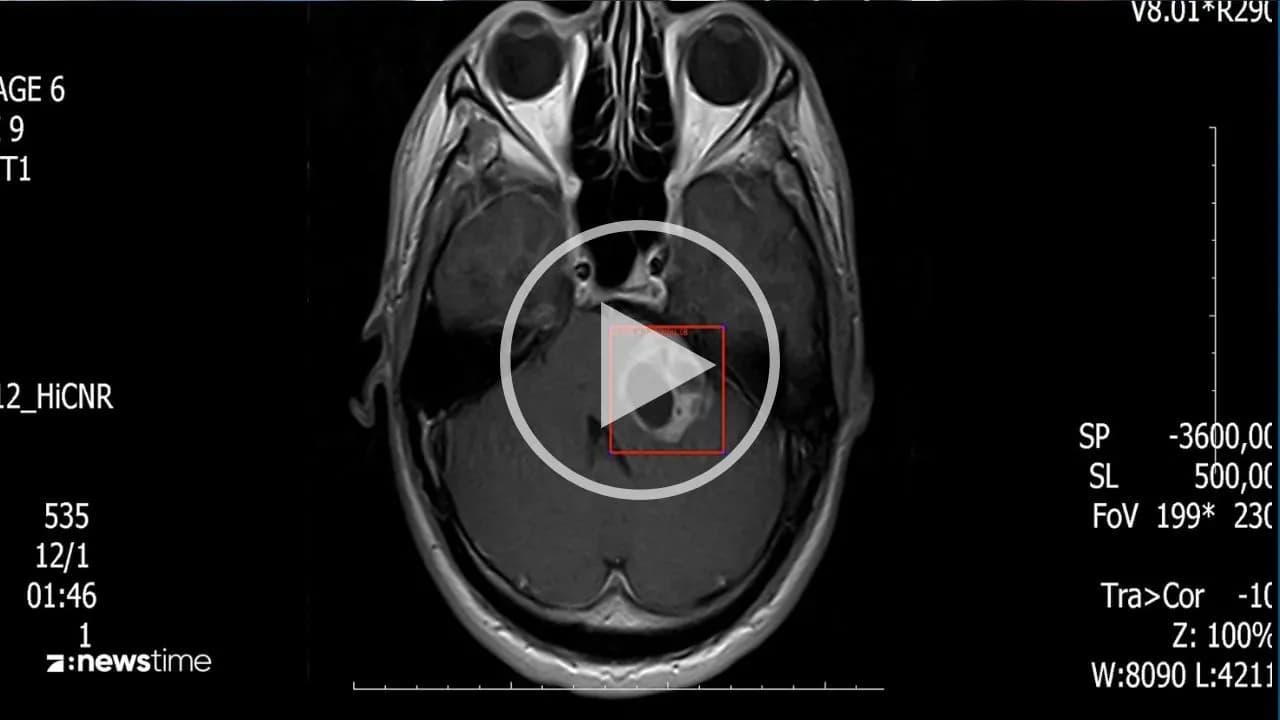

von Beyza PütünDer neue KI-Krebstest der Charité in Berlin soll in nur wenigen Sekunden über 170 Krebsarten erkennen. (Symbolbild)

Es ist schwierig, einen möglichen Tumorzu erkennen, wenn dieser ungünstig gelegen ist. Vor allem bei Hirntumoren kann eine Biopsie riskant sein. Die Charité in Berlin liefert jetzt eine Alternative zu risikoreichen Eingriffen. Auf der Basis des Künstlichen-Intelligenz-Modells mit dem Namen CrossNN können ohne riskante Eingriffe 170 Krebsarten erkannt werden. Wie das funktionieren kann, sehen Sie im folgenden Video: